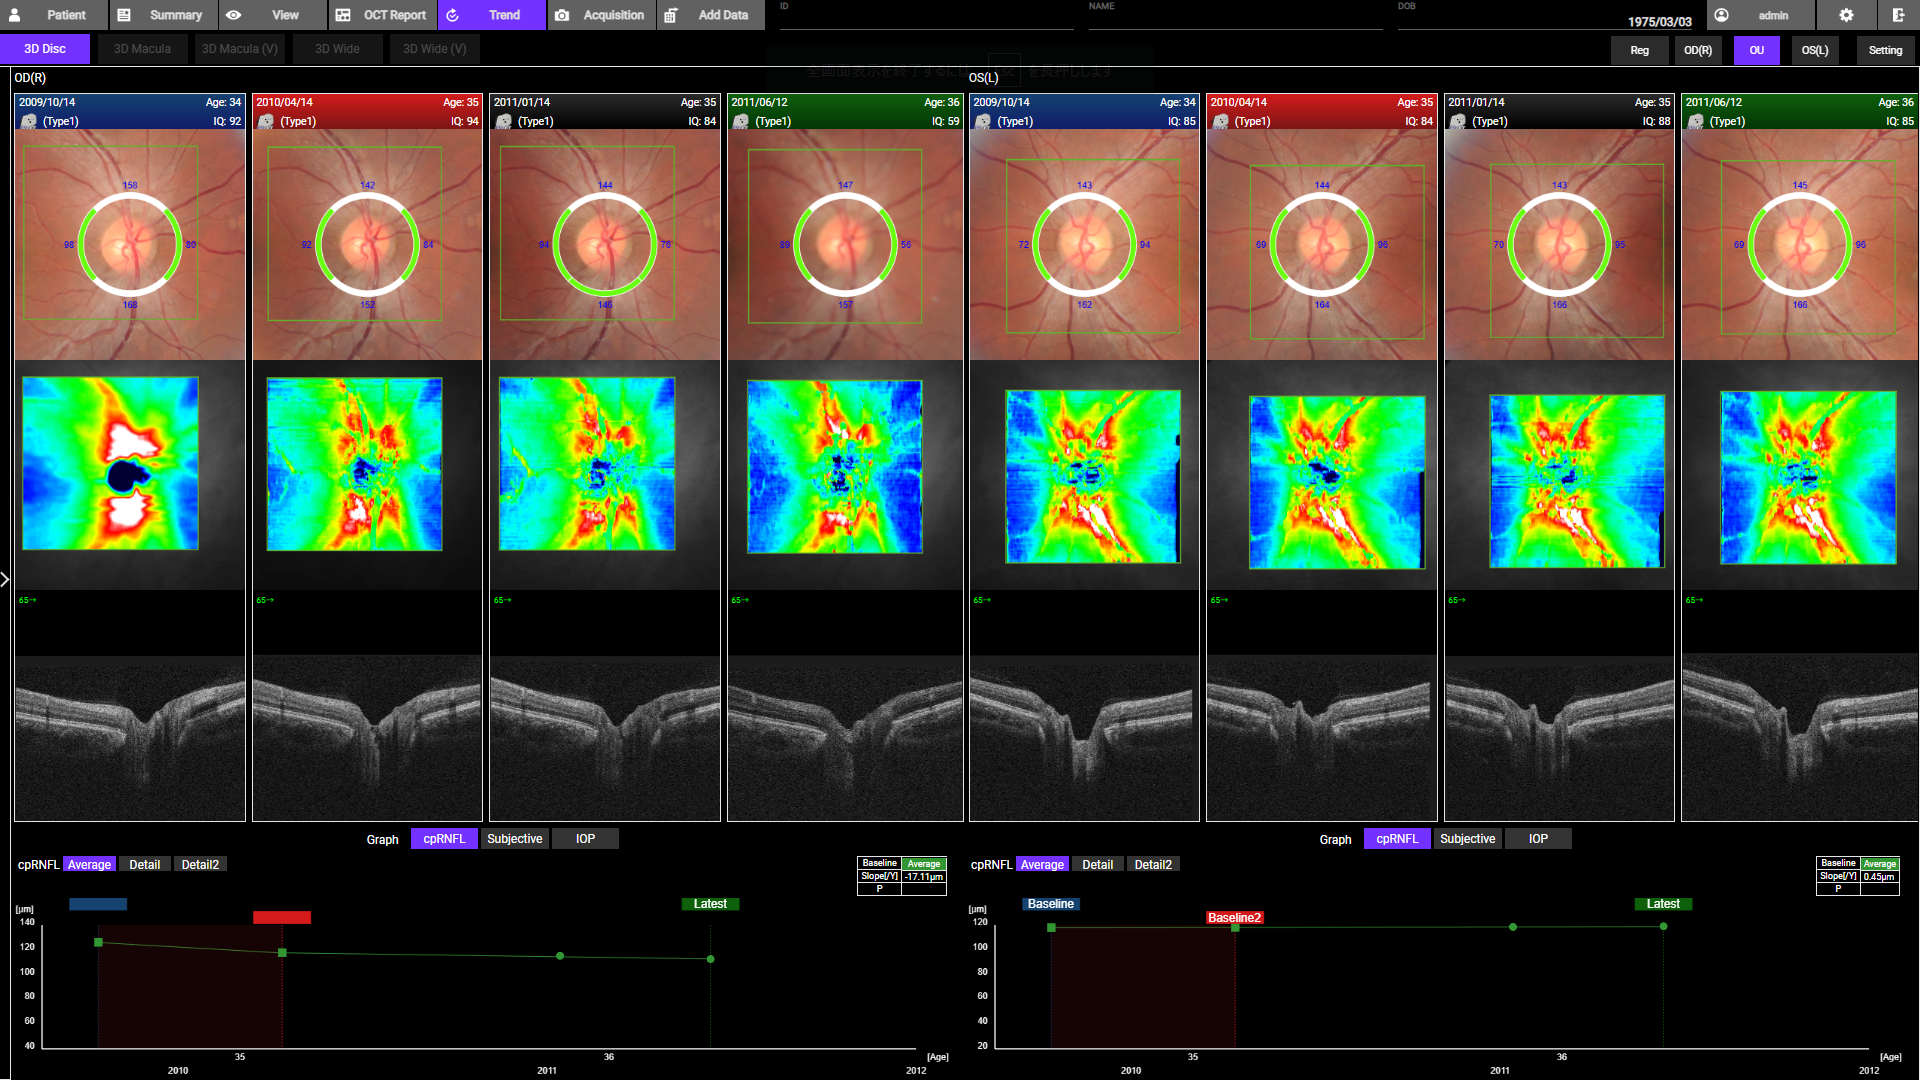

- Follow-Up Funktion: Automatische Wiedererfassung derselben Region für präzise Verlaufsvergleiche

- Komplette Glaukom- und Vorderabschnitts-Analyse: 12×9 mm 3D Wide Scan für Sehnerv und Makula in einer Aufnahme; optionale Vorderabschnitts-Bildgebung für umfassende Diagnostik